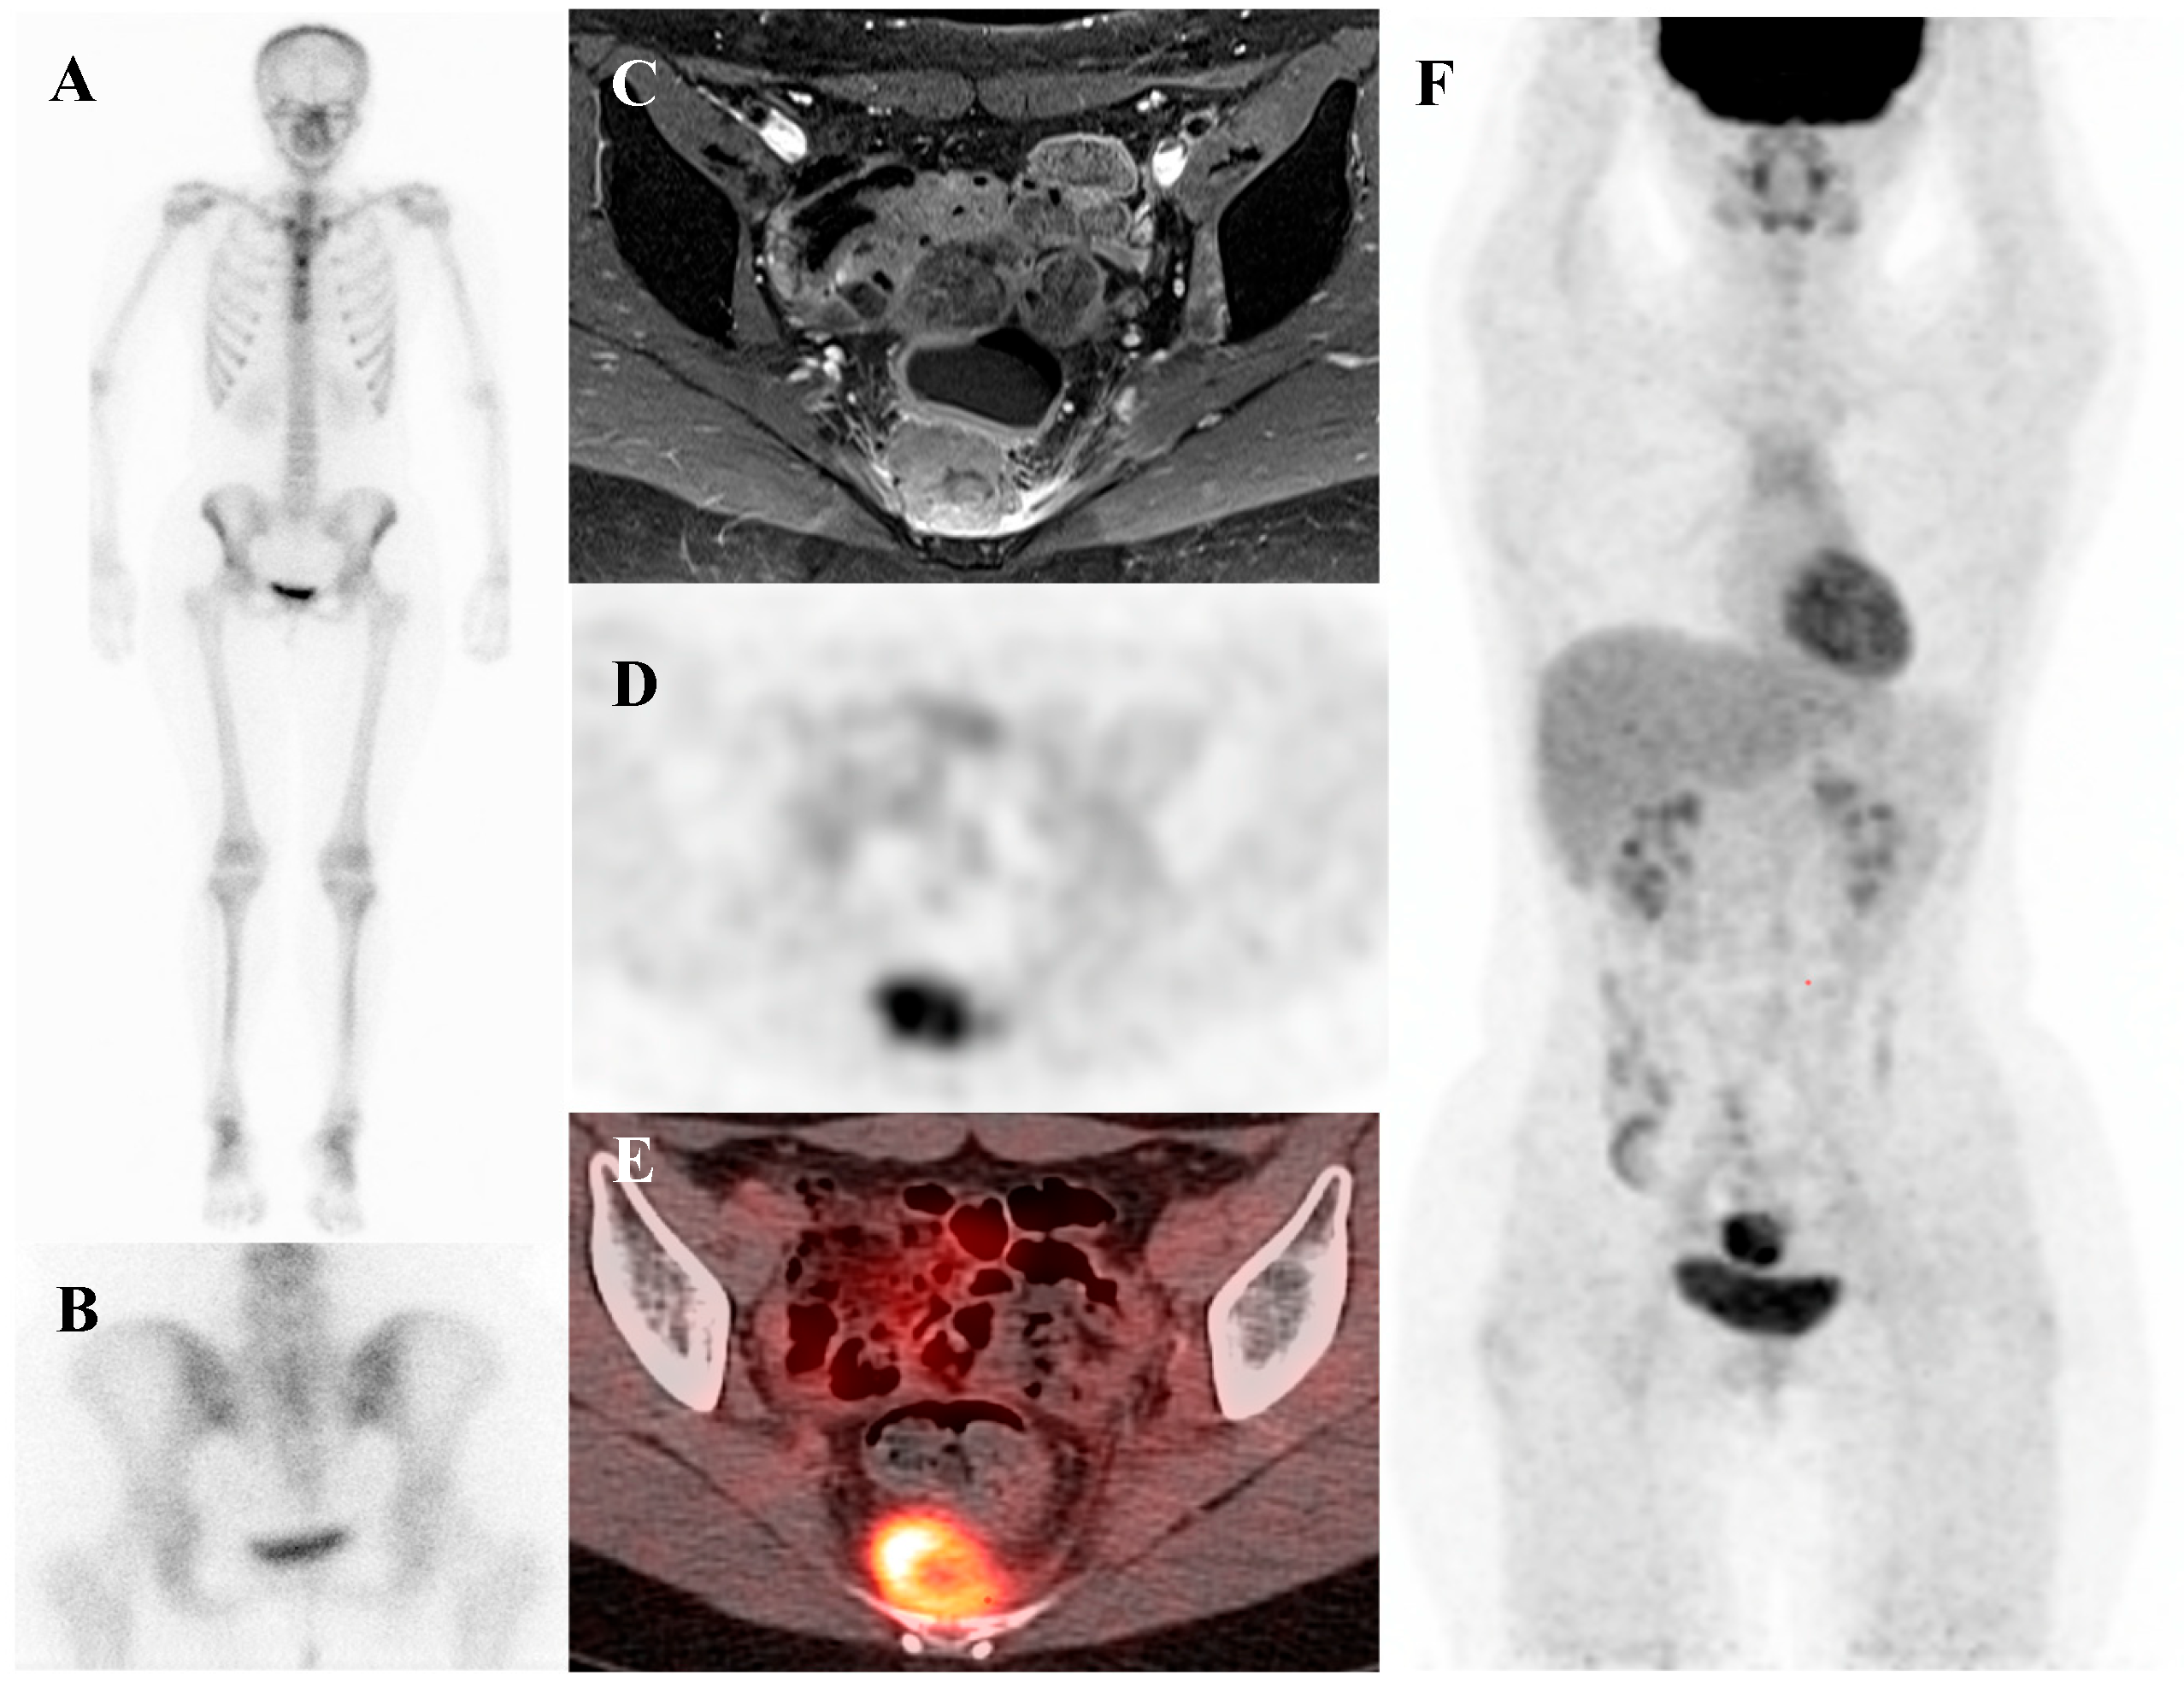

Patients with Ewing sarcoma are at high risk for disease recurrence, which most often occurs in the lungs or bone and carries a poor prognosis [45,46]. [18F]FDG PET/CT is an extremely valuable tool for post-treatment surveillance and for the early detection of recurrent disease [18,25]. The appearance of new, focal [18F]FDG-avid lesions on follow-up scans is highly suspicious for recurrence and prompts further investigation and salvage therapy. Whole-body nature of [18F]FDG PET/CT is ideal for detecting recurrence at any potential site. Figure 2 demonstrates a representative case in which bone scintigraphy failed to reveal recurrent disease, whereas [18F]FDG PET/CT clearly identified the metabolically active presacral mass, subsequently confirmed as recurrent Ewing sarcoma after surgical excision.

Figure 2.

A 19-year-old female with recurrent Ewing’s sarcoma. (A,B) Bone scintigraphy shows no abnormal uptake on both anterior and posterior view. (C) T1 fat-suppressed magnetic resonance imaging demonstrates a lobulated, enhancing presacral mass with invasion of the sacrum. (D–F) [18F]FDG positron emission tomography/computed tomography reveals intense uptake of the mass (SUVmax 9.0). Surgical excision confirmed recurrence of Ewing’s sarcoma.